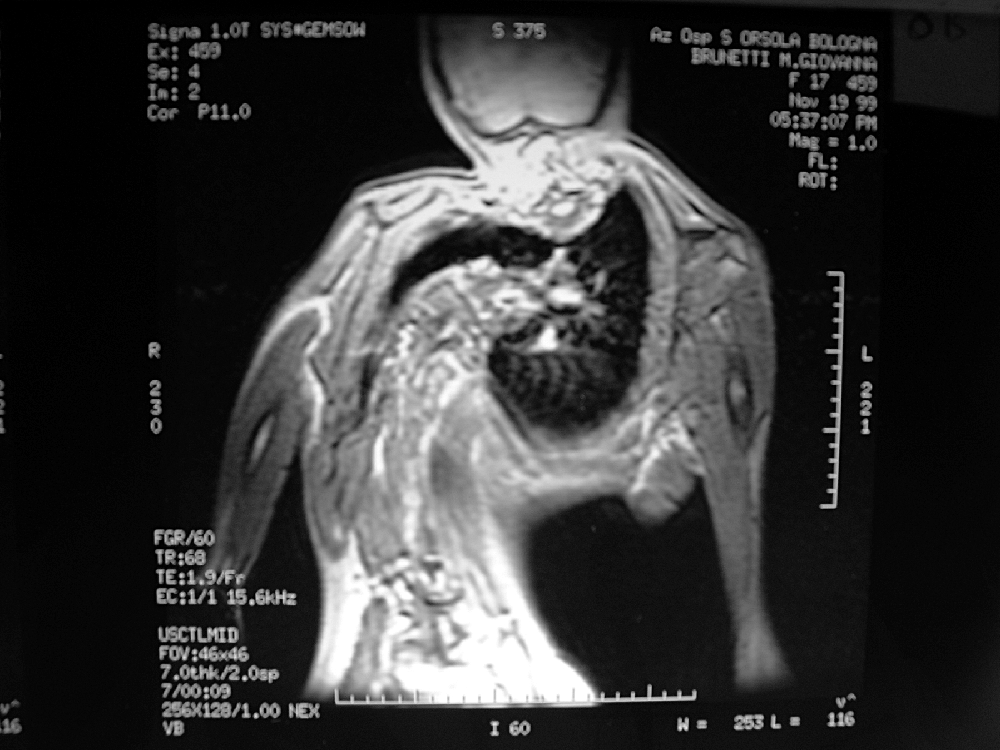

The First Case A 17 Year Old Male Patient Whose Brother Also Had Download Scientific Diagram

The First Case A 17 Year Old Male Patient Whose Brother Also Had Download Scientific Diagram from www.researchgate.net